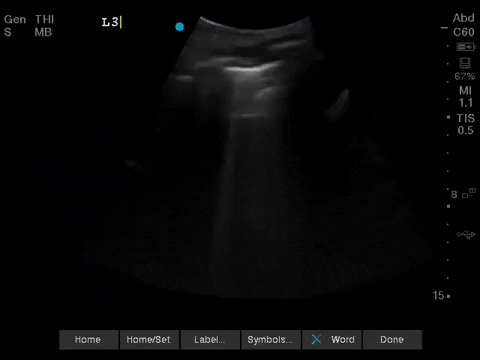

The POCUS team was asked to specifically to assess her lungs to help determine the cause of her dramatically increased oxygen requirements.

Before giving their clinical interpretation of the LUS findings, the POCUS team also scanned the heart and vasculature to obtain a more complete picture.

1. When scanning the lungs, a comprehensive, bilateral lung scan is far superior to a single clip; as this will offer more information and permit an interpretation based on the overall pattern of findings. Had this patient only had the R1 area scanned, for example, we may have reached the erroneous conclusion that her hypoxemia was likely due to pulmonary edema.